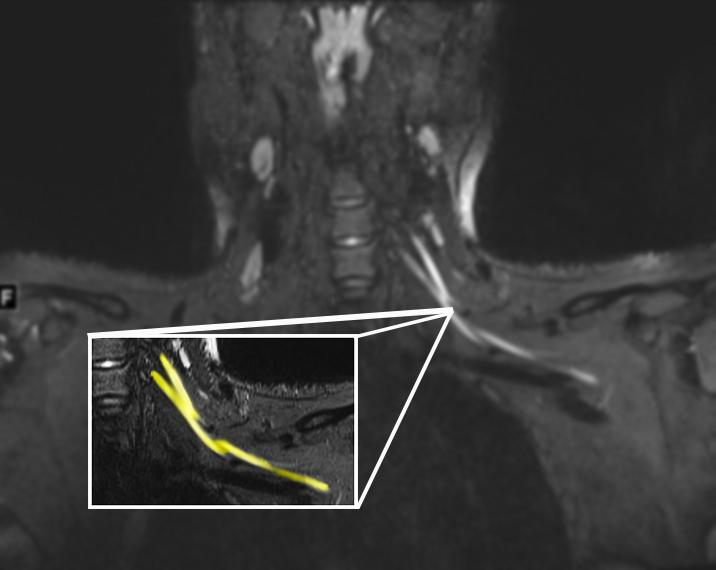

From www.eurekalert.org

MRI shows nerve damage in neck [IMAGE] EurekAlert! Science News Releases What Can An Mri Detect For Nerve Damage  It can help diagnose nerve abnormalities, such as. Find out the conditions that may be diagnosed by mri and the. Mr neurography (mrn) is a technique that images nerves anywhere in the body using mri scanners. Mri can help diagnose peripheral nerve injury by providing detailed images of the nerves and surrounding tissues. Can an mri show nerve damage? Conventional. What Can An Mri Detect For Nerve Damage.